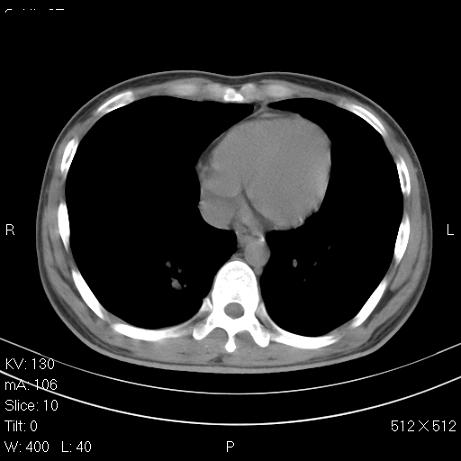

标题: CT7171B:补充治疗后2周复查 [打印本页]

标题: CT7171B:补充治疗后2周复查

治疗后2周复查,请讨论

结合以前的ct片,还是考虑肺挫伤,吸收多了。

支持:创伤性湿肺。现肺挫裂伤(出血 积气)大部分吸收。建议继续治疗!

结合以前的ct片,支持创伤性湿肺。现大部分吸收。

支持:创伤性湿肺、肺挫裂伤。现肺挫裂伤(出血、渗出、液气腔)大部分吸收。建议继续治疗!

支持:创伤性湿肺、肺挫裂伤。现肺挫裂伤(出血、渗出、液气腔)大部分吸收.

结合老片支持创伤性湿肺、肺挫裂伤。

经治疗后病灶明显吸收,考虑创伤性湿肺、肺挫裂伤